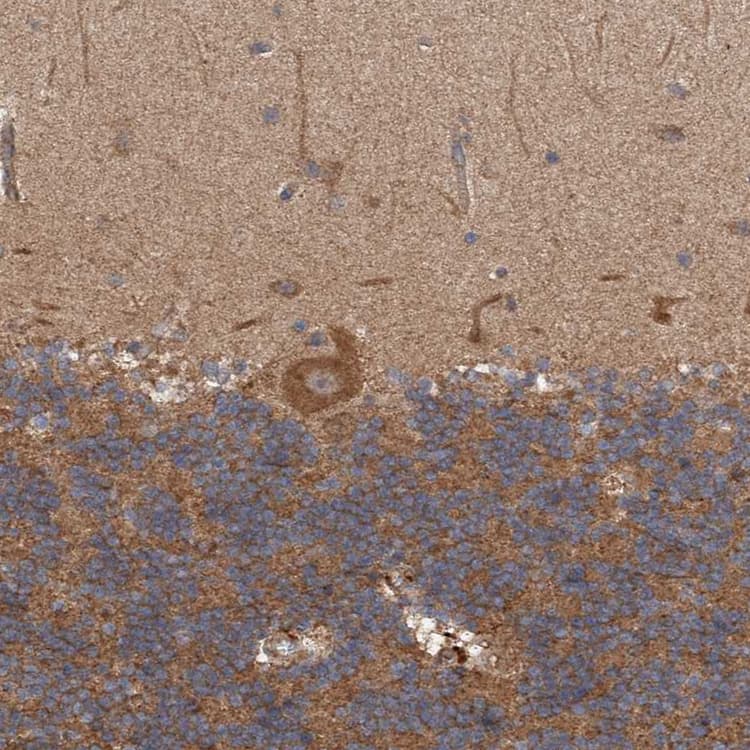

Rabbit Polyclonal TRIM16 antibody. Suitable for IHC-P, WB and reacts with Human samples. Cited in 1 publication. Immunogen corresponding to Recombinant Fragment Protein within Human Tripartite motif-containing protein 16 aa 50-250.

Applications IHC-P, WB

Species Reactivity Human